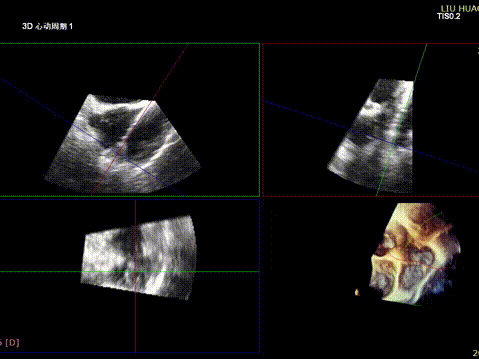

The operation was performed in a hybrid operating room and completed under the guidance of real-time three-dimensional transesophageal echocardiography (3D TEE) and X-ray fluoroscopy throughout the entire process.

1.Intraoperative baseline assessment of regurgitation severity

2.Placement of large sheath and delivery system under ultrasound guidance

3.Steer and rotate the delivery system to target the lesion, and implant the anchor screw via the 3D MPR plane

4.Land the clamping arms after orientation adjustment, and close the clamping arms slowly

5.Perform the same procedure for the second clip; the clip morphology is stable under 3D imaging